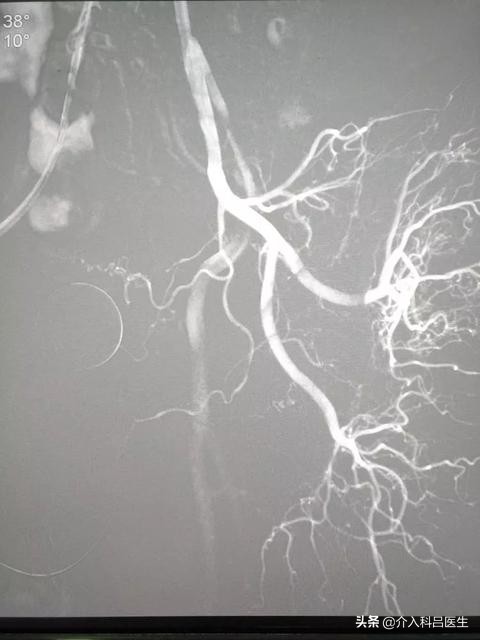

看过我的科普的朋友都知道介入治疗,对于严重的前列腺增生效果立竿见影从根源上解除攻击病灶生长的营养源,将这些血管栓塞,这样病灶失去了营养术后就会慢慢枯萎消失脱落,那么病灶就解除了创伤只有米粒那么大,出血量也几乎等于没有术后就能下地行走,创伤非常小,恢复也很快,很多患者术后三天就恢复了,排尿通畅,而且对身体的损伤,这对于患者非常有利因为很多年纪大的患者,伴随有很多基础疾病,对于创伤太大的手术是无法接受的介入治疗的创伤很小,让患者少遭罪,还能治好病,可以说是一劳永逸,术后也不用再吃药,因为前列腺增生的药跟高血压药一样,一旦开始服用,是不能停药的,非常麻烦。